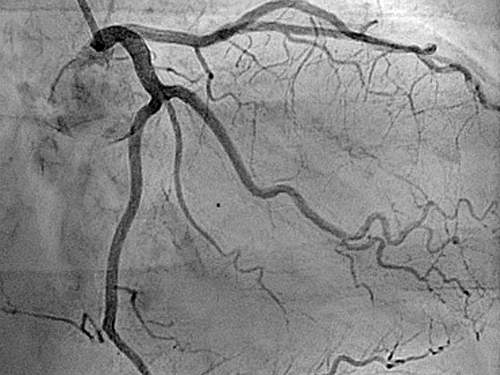

Coronary Angiogram

A coronary angiogram is a diagnostic X-ray procedure that uses a contrast dye to identify blockages or narrowing in the heart’s blood vessels.